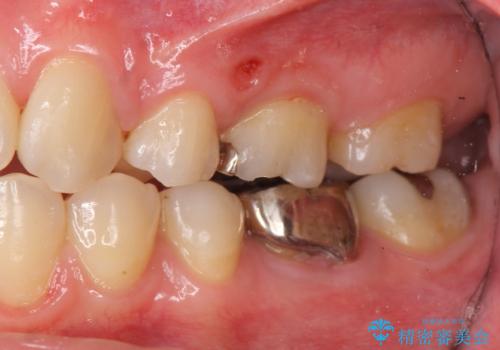

ただし、元のインレーが遠心マージンが縁下だったため、矯正治療後に歯ぐきの厚みを減らして、しっかり歯ぐきの上にマージンラインが来るように整える手術(ディスタルウェッジ)を行いました。

レーザーや電気メスで分厚い歯肉を焼いても一時的で、やがてまた元のように歯ぐきが上まで増殖しますので、今回は骨の厚みも調整し、7番の遠心を出来るだけ下げました。